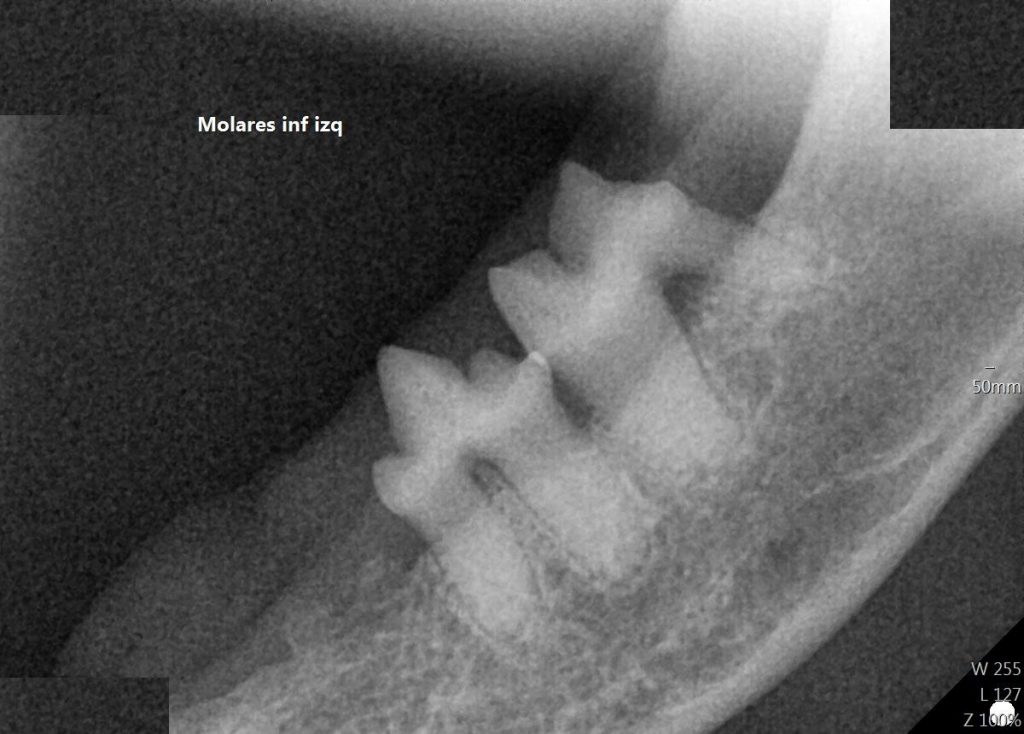

La radiografía dental es fundamental para tratar patología orales y ver el estado interno de las piezas dentales. Al igual que nuestro dentista nos hace radiografías para evaluar el estado de nuestros dientes en

nuestras mascotas pasa exactamente lo mismo, en especial cuando tenemos que hacer limpiezas de boca en animales que acumulan mucho sarro y que presentan infecciones en la zona de la boca.

Las radiografías dentales nos ayudan a evaluar los peligros que puede haber al extraer determinados dientes, y nos permiten apreciar el daño que hay en el hueso y la raíz dentaria de una manera mucho más precisa que las radiografías convencionales.